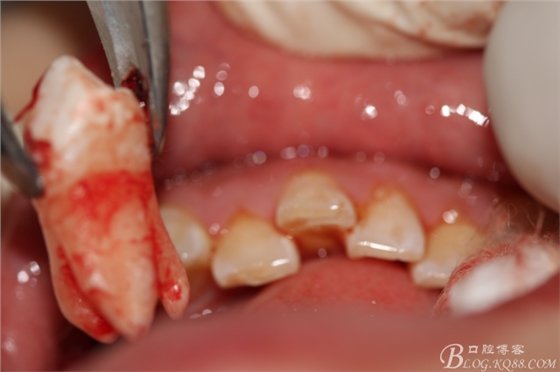

4.術(shù)中拔除下頜第一前磨牙照片